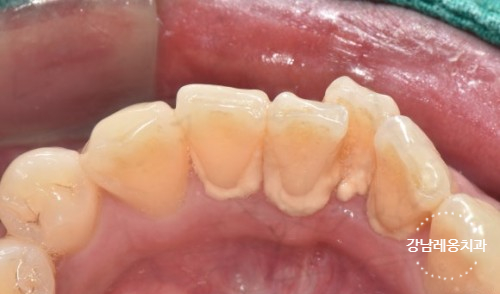

치아 스케일링은 치아 표면뿐만 아니라

잇몸 주변과 치아 사이사이

치석과 치태를 제거하는 치료입니다.

칫솔로는 닿지 않는 어금니 안 쪽과

치아 사이 사각지대에 있는 음식찌꺼기는

좀처럼 씻겨지지 않아

세균과 함께 굳어져 치석이 되기 쉽습니다.

이 치석을 방치하면 잇몸 염증,

치주질환으로 이어질 수 있습니다.

스케일링 중 출혈은 치석이 오래 쌓이면서

잇몸이 약해지고 작은 자극에도

쉽게 피가 나는 상태이기 때문입니다.

잇몸이 퇴축되어 보이는 것은

스케일링 치료때문이 아닙니다

치석이 사라지며 본래의 모습이 드러나는 것입니다.

그동안 치석이 잇몸처럼 붙어 있었기에

치석이 많을 수록 스케일링 후

공간이 생긴 것처럼 느껴질 수 있습니다.